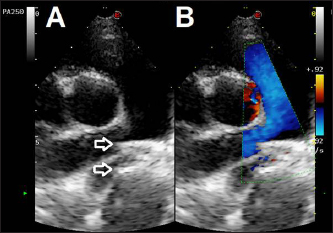

Thoracic radiographs showed left-sided cardiomegaly and pulmonary over circulation (Fig. 1). A transthoracic echocardiogram revealed severe left atrial and left ventricular dilation: left atrium/aorta (LA:Ao): 2.04, reference value: <1.6, normalized left ventricular internal diastolic diameter (LVIDDN): 3.02, reference value: ≤1.7) and large PDA, with an approximate minimal ostium and ampulla diameters of 5.2 and 10.3 mm (Fig. 2). Doppler echocardiography confirmed left-to-right flow across the PDA with a pressure gradient of 102 mmHg in systole and 41 mmHg in diastole. Mild mitral regurgitation was also noted.

Fig. 2. Transthoracic echocardiographic (right parasternal short axis view, optimized for duct visualization). (A) PDA visualization and its measurement and (B) left to right flow on CFM Doppler (dual mode).

Echocardiographic checks at 3 and 24 hours showed complete PDA closure, correct positioning of the mVSDO (Fig. 5), and a clear reduction in left heart volume overload (LA: Ao decreased from 1.72 to 1.3, LVIDDN decreased from 2.49 to 2.43).